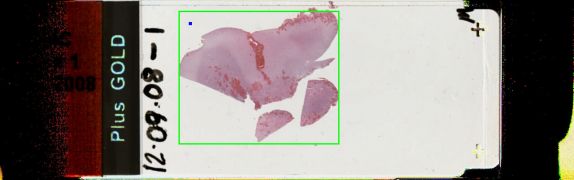

The slides showed choroid plexus with amorphous eosinophilic material, metaplastic lamellar bone and calcification.

The diagnosis was amyloidosis in the choroid plexus.

Slide Image:

view high resolution slide image